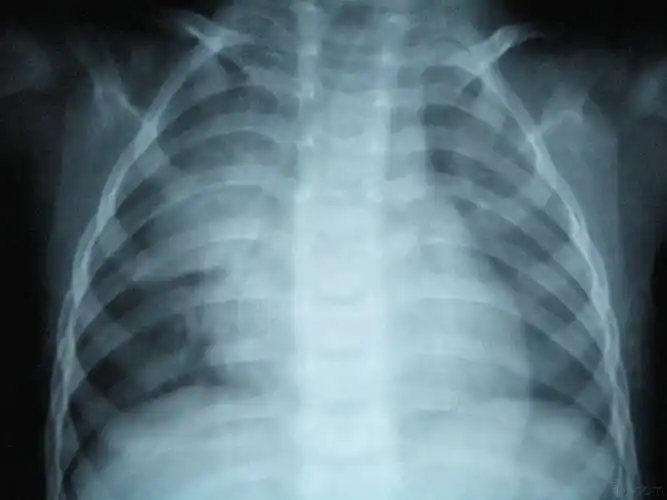

新生儿30天得肺炎,现在在妇幼icu,这是胸片,很严重吗